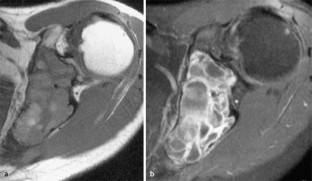

MRI morphology of bone tumors and tumor-like lesions

Für das Staging und die Charakterisierung von Knochentumoren und tumorähnlichen Läsionen ist in der Magnetresonanztomographie (MRT) der Einsatz von Spinechosequenzen erforderlich. Die MRT hat nur einen geringen Stellenwert in der Bestimmung der Dignität. Obwohl viele Knochentumoren und tumorähnliche Läsionen eine vergleichbare Morphologie in dieser bildgebenden Modalität aufweisen, können einige Tumorentitäten mittels MRT recht zuverlässig diagnostiziert werden. Hierzu zählen Knorpeltumoren, die solitäre und aneurysmatische Knochenzyste, der Riesenzelltumor, fetthaltige Läsionen und bis zu einem gewissen Grad auch das Osteoidosteom und das Osteoblastom. Es werden praktische Tipps gegeben, wann bei Tumorverdacht die MRT eingesetzt werden sollte, wie bei einem zufällig bei einer MRT gefundenen Tumor die Untersuchung modifiziert werden sollte und welcher Tumor vorliegen könnte.

Spin-echo sequences are mandatory at MRI for staging and characterization of bone tumors and tumor-like lesions. MRI is of minor value in the estimation of the malignant potential of an osseous lesion. Although many bone tumors and tumor-like lesions present similar morphology at MRI, some entities can be diagnosed with good reliability. These include chondrogenic tumors, solitary and aneurysmal bone cysts, giant cell tumors, lesions containing fatty tissue and, to a certain extent, osteoid-osteomas and osteoblastomas. Practical advice is given regarding when to perform a MRI study in cases of tumor suspicion. Further advices are given for cases a tumor is found incidentally at a MRI study, how to modify the study and which kind of tumor may be present.